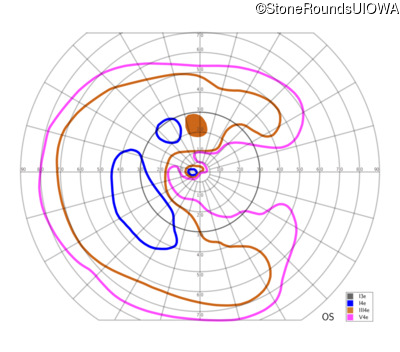

This 81 year old man began using a flashlight to read menus in his 40's. At age 75 his ophthalmologist noticed abnormal fundus findings and referred him to a retina specialist.

| OD | OS | ||

|---|---|---|---|

| Late Onset Retinal Dystrophy | C1QTNF5 | Ser163Arg AGC>AGA | AD |